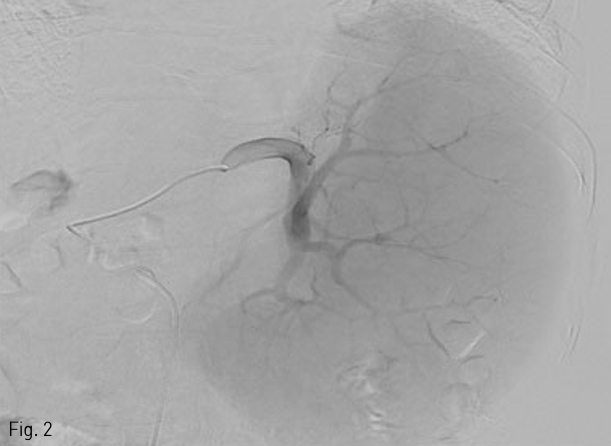

5 Fr Yashiro catheter (Terumo, Tokyo, Japan)를 복강동맥을 통해 비장동맥에 삽입한 후 혈관조영술을 시행하여 비장동맥의 분지들을 먼저 확인하였다 (Fig. 2). 0.021 inch guide wire (GT guide wire; Terumo)와 2.7 Fr microcatheter (Progreat; Terumo, Tokyo, Japan)를 이용하여 co-axial technique으로 middle segmental artery가 분지된 이후 splenic hilum에서의 비장동맥에 12mm×3cm 1개, 10mm×3cm 3개의 platinum coils (IDC: Interlocking Detachable Coil; Boston Scientific, Tokyo, Japan)와 gelfoam (Cutanplast, Mascia Brunelli Spa, Milano, Italy), N-butyl cyanoacrylate (NBCA; Histoacryl; B.Braun, Melsungen, Germany)와 Lipiodol (Guerbet, Paris, France) 1:4 혼합물을 이용하여 superior, inferior segmental artery를 색전하였다 (Fig. 3). 색전 후 비장동맥 조영술에서 splenic hilum level에서 원위부 색전이 이루어진 것을 확인하였다(Fig. 4).

Fig 3

Road map image shows deployment of several detachable coils into the inferior branches of splenic artery during embolization.